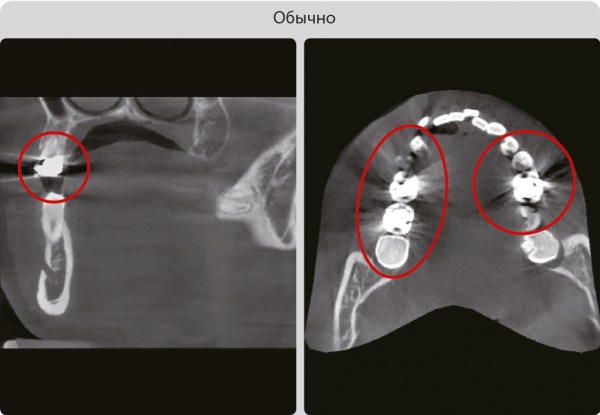

SMART MAR – алгоритм уменьшения появления артефактов от металлов при томографии

Свечение металла значительно снижает диагностическую ценность 3D исследований Технология SMART MAR обеспечивает минимальные потери качества изображения при наличии металла у пациента.